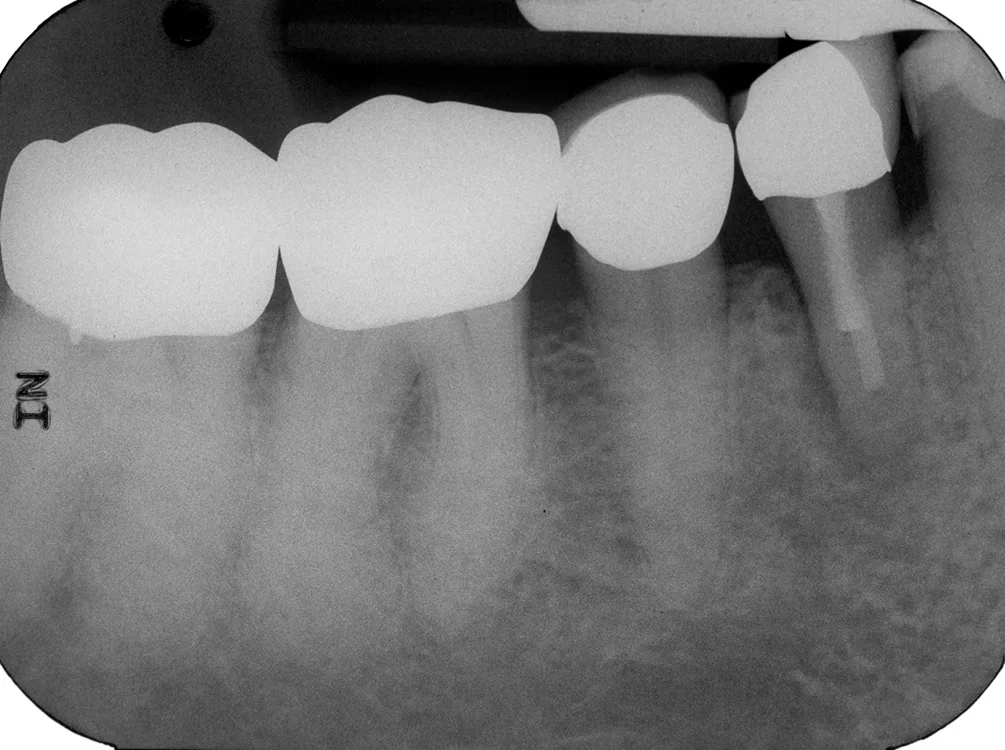

Mit zunehmendem Alter kommt es zu Veränderungen in Knochenstruktur und -metabolismus mit Abnahme der Knochendichte und -masse, reduzierter Stoffwechselaktivität, Rückgang der Zahl der Osteoblasten und Osteozyten sowie Zunahme der Osteoklastenaktivität [46]. Die Zusammensetzung und die Struktur des Dentins ändern sich mit zunehmendem Alter: Der Anteil sklerotischen Dentins nimmt zu, der Anteil kollagener Faser nimmt ab, dadurch erhöht sich die Anfälligkeit für Längsfrakturen (Abb. 1). Der Durchmesser der Dentintubuli wird geringer. Die Veränderungen in der Schmelz- und Dentinstruktur manifestieren sich auch im Verlust der Transparenz und gelblicher Zahnverfärbung sowie dem Auftreten von Schmelzrissen (Abb. 2) [46,48].